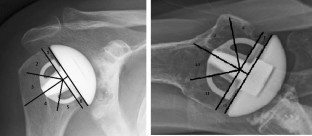

Fig. 1

Fig. 2

Fig. 3

Fig. 4

Fig. 5

Fig. 6